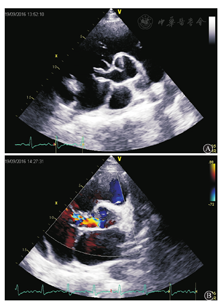

患者男性,24岁,因"间断胸痛、发热1月余"于2016年9月19日入院。入院1个月余前睡眠时无明显诱因突发右前胸撕裂样疼痛,持续约半小时后自行缓解,未予重视。数天后出现咳嗽、咳白色泡沫痰,后出现发热,伴畏寒、寒战、肌肉酸痛,体温每日上午正常,下午升高至39℃左右,偶有活动后心悸、胸闷,休息5~6 min可缓解,伴乏力,活动耐量较前下降。于当地医院查胸部CT(2016年8月5日)示:右下肺门旁囊实性占位性病变,考虑良性;心脏大。予阿米卡星抗感染治疗效果不佳,体温峰值升至39.8℃。2016年9月2日查血常规未见异常,高敏C反应蛋白84.1 mg/L,血培养两次均阴性。超声心动图:LVEF 54%,主动脉无冠窦呈一囊袋状结构向右房膨出,顶部可见破裂口,主动脉无冠窦向右房持续分流;全心大,肺动脉内径增宽,心包腔内可见少量液性暗区。2016年9月6日复查超声心动图示:靠近外口窦部后壁可见一偏强回声,测范围约10 mm×6 mm。联合心外科会诊,考虑"感染性心内膜炎,瓦氏窦瘤破裂",予万古霉素+亚胺培南抗感染治疗,患者体温峰值逐渐降至正常,入我科前2 d体温峰值再次升高至37.5℃,为进一步诊治收入我科。患者病程中无咯血、盗汗,无活动后喘息及下肢水肿,无皮疹、关节痛。既往体健,否认幼年时活动后呼吸困难、发绀、蹲踞病史,否认幼年关节肿痛、肾炎病史。未婚,曾服兵役3年,家族史无特殊。体格检查:体温37.6℃,脉搏123次/min,呼吸17次/min,血压148/76 mmHg。身高183 cm,体重78 kg。皮肤黏膜无黄染,双肺未及干湿啰音。心尖搏动弥散,叩诊全心增大,心率123次/min,律齐,三尖瓣听诊区可闻及3/6级舒张期杂音。腹软无压痛,肝脾肋下未及。双下肢无水肿。入院诊断:主动脉窦无冠窦窦瘤破裂,感染性心内膜炎?全心扩大,主肺动脉扩张,心包积液(少量),左心功能减低。入院后完善化验检查:血沉63 mm/第1小时,C反应蛋白19.6 mg/dl,降钙素原0.16 ng/ml,肌钙蛋白T 0.007 ng/ml,肌酸激酶-同工酶1.02 ng/ml,B型利钠肽217.60 pg/ml。心电图示窦性心动过速,各导联波形未见明显异常。复查超声心动图:各房室内径大,主动脉窦无冠窦瘤样改变,向右房膨出,窦瘤顶部连续性中断约8 mm(图1A)。心包腔内后区探及宽约9 mm液性暗区,LVEF 48%。多普勒:主动脉无冠窦可探及五彩血流分流至右心房(图1B),收缩期为著,流速最高4.8 m/s。心脏MRI:无冠窦呈囊袋样突向右心房,并可见向右心房分流,结合超声心动,符合无冠窦瘤破裂;左、右心室及右心房增大;LVEF 46.8%,心包积液(中量)。予万古霉素+亚胺培南抗感染治疗,患者体温峰值降至38.5℃以下。2016年9月20日转入心脏外科继续原方案抗感染治疗,2016年9月26日行主动脉窦瘤破裂修补术+右胸腔肿物切除术,术中见心包内中量淡黄色积液,右心房室扩大,主动脉无冠窦瘤破入右心房,瘤蒂根部直径约1 cm,未发现明确赘生物。右胸腔肿物质硬,直径约6 cm,边界清。术后当天体温即降至正常(诊疗过程体温及心率变化见图2)。手术病理结果:右胸腔炎症性肌纤维母细胞瘤,WHO ICD-0编码I级(属于交界性或恶性潜能未定肿瘤)。主动脉窦瘤致密纤维组织,间质明显玻璃样变性,伴片状钙化,结合临床符合主动脉窦瘤(图3)。术后复查超声心动图(2016年10月9日):左室内径大(较前缩小),内未见异常回声团,主动脉窦无冠窦回声增强,未见连续性中断,心包腔内未探及液性暗区。多普勒:主动脉无冠窦修补处未探及分流。出院诊断:主动脉窦无冠窦窦瘤破裂修补术后,左室扩大,主动脉瓣关闭不全(轻),右胸腔炎症性肌纤维母细胞瘤切除术后。

A:超声心动图示主动脉无冠窦呈一囊袋状结构向右房膨出,顶部可见破裂口,与右心房相通;B:彩色多普勒示主动脉窦破裂处可见主动脉无冠窦向右房持续分流